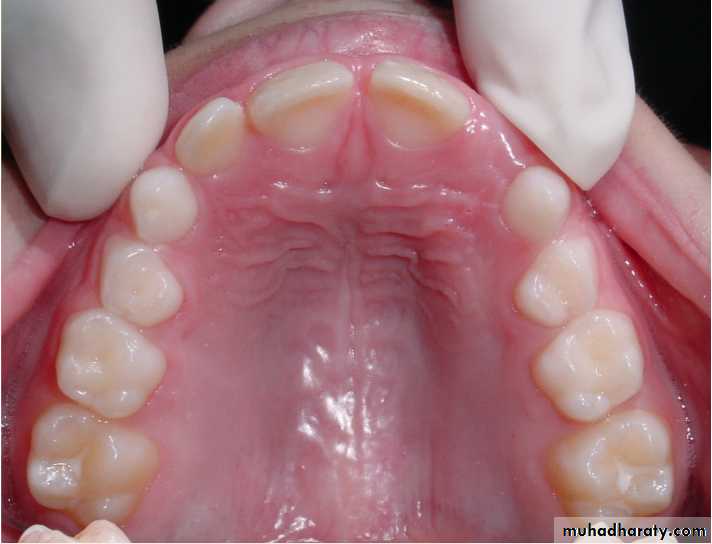

Morphological difference between primary and permanent teeth

The crowns of primary teeth :

are shorter

have a narrower occlusal table

have a more pronounced cervical constriction

have thinner enamel and dentin layers

• crowns of primary teeth :

• have broad flat contact areas between primary molars

Roots of primary molars:

are longer and more slender in relation to crown size

are more flared as they approach the apex in order to accommodate the developing permanent tooth buds

Keys to differentiating primary and permanent teeth:

Color primary teeth white and opaque

Size and contoursDepth of anatomy

Age of child

Location of teeth (counting)